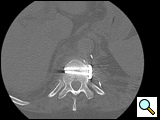

After completion of the spinal procedure, reorientation of the thoracic surgeon by the spinal surgeon is performed, including visualization of the implanted hardware and an explanation of the procedure that was performed (Figures 9a-c). Hemostasis is secured, the chest irrigated, and the posterior mediastinum is inspected for lymph leak (the presence of a CSF leak must be ruled out by the spine surgeon prior to this point in the operation). The diaphragm, if mobilized, is reattached to the fascia of the posterior chest wall with interrupted horizontal 0 prolene sutures or is anchored around the rib. A 28 Fr chest tube is placed in the posterior mediastinum and the chest is closed in a standard fashion. Postoperative spine imaging is necessary to demonstrate adequate position of the hardware and correction of the vertebral defect (Figures 10a-e, Video).

| Figure 10a-e: CT of spine after fixation | Figure 10b | Figure 10c |